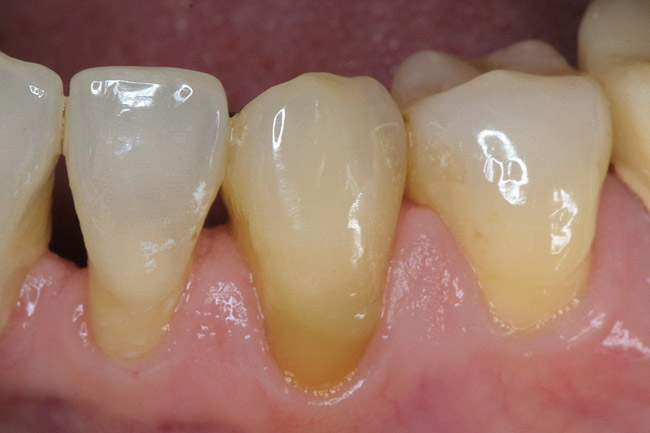

Figure 7  The "single-tooth" bleaching tray has no reservoir or spacers and extends onto the gingiva 1 mm to 2-mm, but avoids frenum movements. The teeth not to be bleached have the tooth molds removed from the tray while maintaining the intact tray.

Figure 7

Figure 8  The single-tooth bleaching tray extended further onto the palate than the traditional tray to preserve the tray integrity when the adjacent teeth molds were removed from the tray. The tray edges are hidden behind rugae and go onto the tissue in all areas.

Figure 8